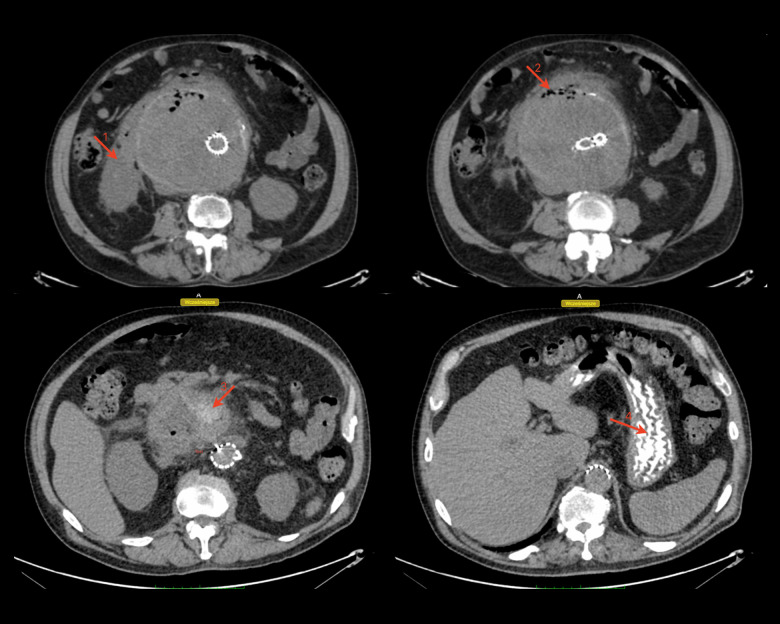

主动脉-十二指肠瘘(ADF)是主动脉和十二指肠之间的交通,需要紧急主动脉修复。然而,它经常导致危及生命的并发症。因此,早期和适当的诊断方法是必要的,以提供充分的治疗。本报告描述了一名68岁男性患者,在使用口腔造影计算机断层扫描(CT)对14厘米腹主动脉瘤(AAA)进行紧急血管内修复后出现肛肠-十二指肠瘘的病例,并讨论了延迟治疗和ADF管理的后果。我们报告一例68岁白人男性腹部腹胀,经进一步检查诊断为AAA,并通过血管内动脉瘤修复(EVAR)成功治疗。然而,1年后,发现了一个漏洞,尽管医生的努力,但由于患者连续数年推迟治疗,整体治疗变得复杂。动脉瘤继续扩大,直到达到14厘米。尽管血管内瘘成功修复,但通过CT和口腔造影诊断为十二指肠主动脉瘘(DAF)。患者保守处理动脉瘤囊引流和抗生素治疗,减少了动脉瘤囊的大小。尽管进行了早期诊断和干预,但由于进一步的并发症,患者的病情恶化,最终导致死亡。结论:本病例报告表明,在其他方法无法检测DAF的情况下,CT联合口腔造影在检测DAF方面具有潜在的有用诊断作用,并强调了及时干预以预防危及生命的并发症的重要性。然而,需要进一步的研究来探索潜在的机制及其可复制性。

BACKGROUND Aorto-duodenal fistula (ADF) is a communication between the aorta and the duodenum and requires urgent aortic repair. However, it often leads to life-threatening complications. Thus, an early and appropriate diagnostic method is necessary to deliver adequate treatment. This report describes the case of a 68-year-old man with anaorto-duodenal fistula following emergency endovascular repair of a 14-cm abdominal aortic aneurysm (AAA) identified using oral contrast computed tomography (CT), and discusses the consequences of delayed treatment and ADF management. CASE REPORT We present a case of a 68-year-old White man with abdominal bloating, who upon further examination was diagnosed with an AAA, which was successfully treated by endovascular aneurysm repair (EVAR). However, 1 year later, an endoleak was discovered and, despite the physicians' efforts, the overall treatment was complicated due to the patient's continuous postponement of treatment over several years. The aneurysm continued to expand until it reached 14 cm. Despite the successful endovascular repair of the endoleak, a duodeno-aortic fistula (DAF) was diagnosed using CT with oral contrast. The patient was managed conservatively with aneurysmal sac drainage and antibiotic therapy, which decreased the size of the aneurysmal sac. Despite early diagnostic efforts and interventions, the patient's condition deteriorated due to further complications, ultimately resulting in death. CONCLUSIONS This case report demonstrates a potential useful diagnostic role of CT with oral contrast in detecting DAF, in situations when other methods fail to do so, and emphasizes the importance of prompt intervention to prevent life-threatening complications. However, further investigations to explore the underlying mechanism and its replicability are required.